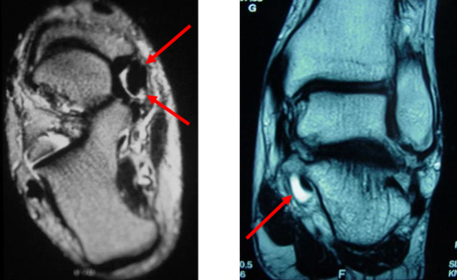

| What is this? | Calcaneonavicular coalition (AKA calcaneonavicular bar or anteater's nose) |